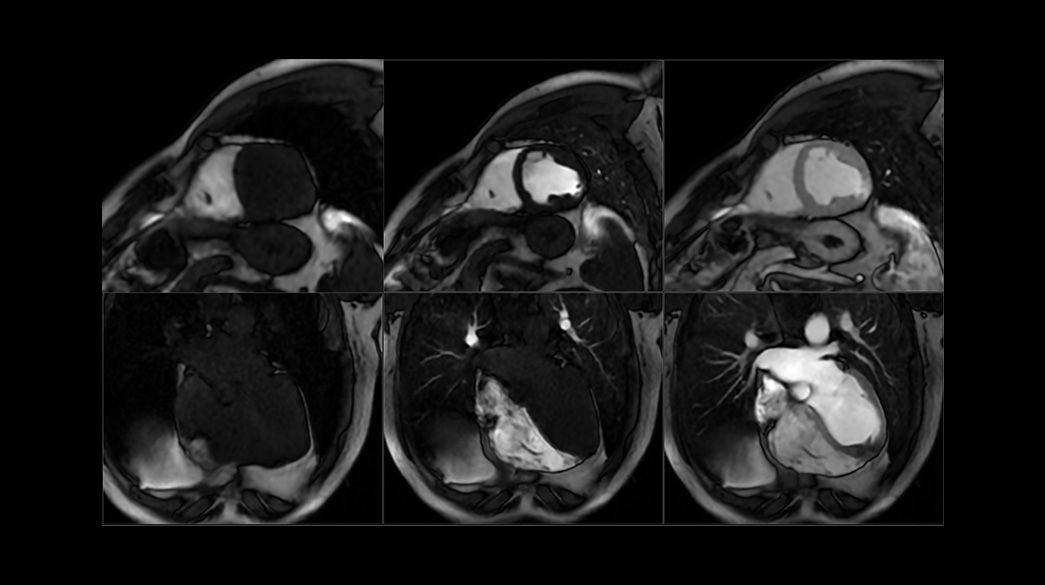

Time Course with MoCo - compatible with AIR™ Recon DL

Used for cardiac first-pass analysis with bolus, now compatible with Motion Correction (MOCO) algorithm for entirely free breathing acquisitions

MDE Plus – compatible with AIR™ Recon DL

Inversion-based cardiac gated acquisition that enhances the contrast between infarcted and normal myocardium, accommodates difficult-to-scan patients

FIESTA Cine

Can be used as a gated or non-gated sequence to assess anatomy and function, with excellent tissue contrast between blood pool, myocardium and valves